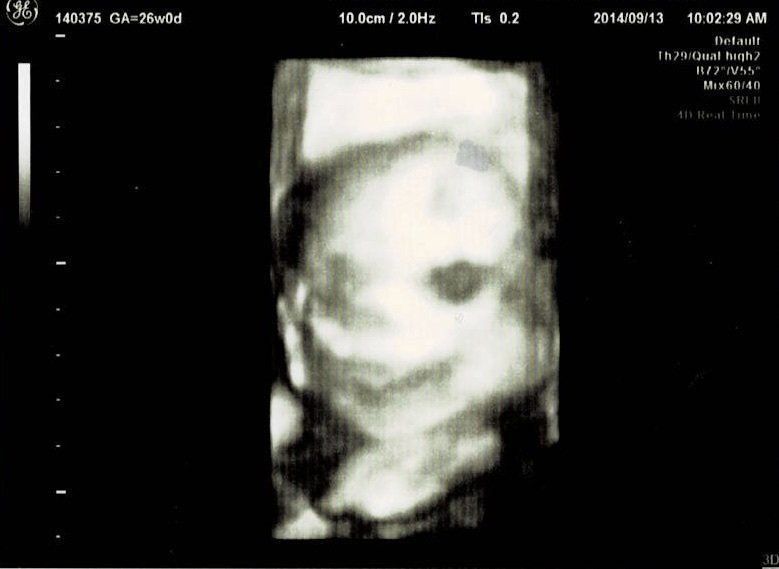

妊娠26週目エコー写真 妊娠中期検査 赤ちゃんのニッコリ顔発見!

妊娠中期検査ということで再び血液検査をしました。今回はHTLV-1(ヒトT細胞白血病ウイルス)とクラミジア抗体のチェックです。さらに血糖検査で、気の抜けたサイダーみたいなブドウ糖液を飲み、60分後の血糖値を測りました。赤ちゃんは前回と同じく、BPD、AC、FLを測ってもらい発育をチェック。赤ちゃんの推定体重は804g。3Dエコーでは、こっちを向いて笑っている(?)表情が見られました。